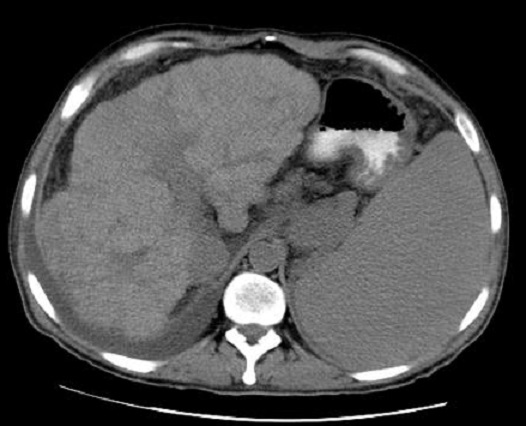

Image TDM de la

cirrhose du foie : Technique radiologique moins

sensible de dignostic cirrhose du foie au debut . Au

stade avance image radiologique TDM de la cirhose du foie

est : Parenchyme du foie est heterogene , hypertrophie

du lobe caude , index C/RL > 0.65 et signe de hypertension

portale : dilatation de la veine porte , veine

splenique , splenomegalie et image de thrombus veineuse .

Image

radiologique TDM d'une cirrhose du foie en coupe

axiale . Le parenchyme et surface du foie est en

nodulaire , heterogene . La lobe caude est

hypertrophie , splenomegalie legere . Index C/RL est

> 0.66 ( cirrhose du foie ) |